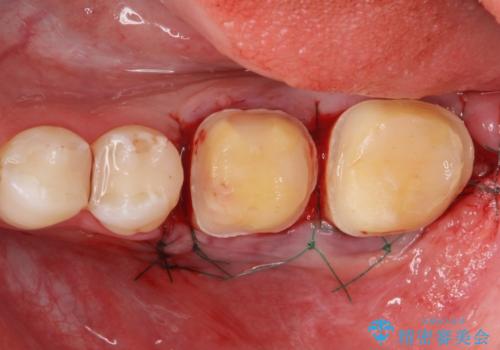

APF(歯肉弁根尖側移動術)

銀歯を外して被せ物の予定でしたが歯の高さが低く取れやすい被せ物になってしまうため歯の高さを変える手術を行いました。

治療後の写真は2週間後の写真です。歯茎の治癒が完全に治るのは半年くらいかかるので半年後に最終的な被せ物を入れる予定です。